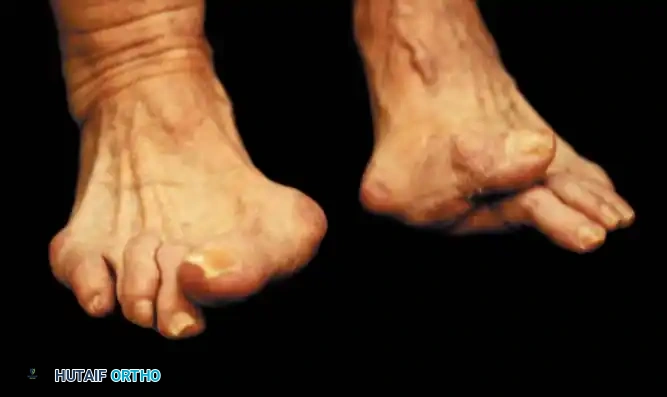

Hallux valgus (lateral deviation of the great toe) is not a single disorder, as the name implies, but a complex deformity of the fi rst ray that frequently is accompanied by deformity and symptoms in the lesser toes (Fig. 78-1). Often the angle between the fi rst and second metatarsals is more than the 8 to 9 degrees usually considered to be the upper limits of normal. The valgus angle of the fi rst metatarsophalangeal joint also is more than the 15 to 20 degrees considered to be the upper limits of normal (Fig. 78-2). If the valgus angle of the fi rst metatarsophalangeal joint exceeds 30 to 35 degrees, pronation of the great toe usually results. With this abnormal rotation, the abductor hallucis, which is normally plantar to the fl exion-extension axis of the fi rst metatarsophalangeal joint, moves further plantarward (Fig. 78-3). In this case, the only restraining medial structure is the medial capsular ligament with its capsulosesamoid portion (inserting into the base of the proximal phalanx) (Fig. 78-4) and capsulophalangeal portion (inserting into the plantar plate). The adductor hallucis, which is unopposed by the abductor hallucis, pulls the great toe further into valgus, stretching the medial capsular ligament (particularly the capsulosesamoid), attenuating this structure, and allowing the metatarsal head to drift medially from the sesamoids. In addition, the fl exor hallucis brevis, fl exor hallucis longus, adductor hallucis, and extensor hallucis longus increase the valgus moment at the metatarsophalangeal joint, further deforming the fi rst ray. The deep transverse intermetatarsal ligament runs between the plantar plates at the metatarsophalangeal joints and does not insert into bone on the adjacent sides of the metatarsal heads. Finally, the sesamoid ridge on the plantar surface of the fi rst metatarsal head (the crista) fl attens because of pressure (abutment) from the tibial sesamoid (Fig. 78-5). With this restraint lost, the fi bular sesamoid displaces partially or completely into the fi rst intermetatarsal space (see Fig. 78-2). In this situation, the patient is bearing less weight on the fi rst ray and more on the lesser metatarsal heads, increasing the likelihood of transfer metatarsalgia, callosities, and stress fracture of a lesser metatarsal.

a congruent metatarsophalangeal articulation; phalangeal osteotomy or distal metatarsal osteotomy, rather than tightening of the medial capsular repair, should be used for further correction. The valgus posture of the great toe frequently causes a hammer toe–like deformity of the second toe (Fig. 78-7). In addition, the splaying of the forefoot makes the wearing of shoes more diffi cult; with shoes that have a narrow toe box, corns often develop, as does bursal hypertrophy over the medial eminence of the fi rst metatarsal head (bunion). With valgus subluxation of the fi rst metatarsophalangeal joint, osteoarthritis frequently develops. In this case, the entire spectrum of hallux valgus is present: varus deformity of the fi rst metatarsal, valgus of the great toe, bunion formation, arthritis of the fi rst metatarsophalangeal joint, hammer toe of one or more toes, corns, calluses, and meta-

Keller Resection Arthroplasty The Keller procedure combines resection hemiarthroplasty of the fi rst metatarsophalangeal joint with removal of the medial eminence of the fi rst metatarsal (Fig. 78-28). Although removing the base of the proximal phalanx decompresses the joint and mobilizes the hallux, allowing marked correction of valgus, the varus of the fi rst metatarsal is not corrected, and maintaining correction of the valgus of the hallux is diffi cult. Other complications of the Keller procedure have been emphasized in the literature to such an extent (with neither the incidence nor the severity of such complications clearly documented) that the indications for this procedure have been limited severely. In our experience, however, complications are uncommon if patients are selected carefully. Modifi cations in the original technique also have allowed expansion of the indications for the Keller bunionectomy. Candidates for the Keller procedure are patients older than 50 years with moderate-to-severe hallux valgus (30 to 45 degrees); intermetatarsal angles of 13 degrees or less, indicating mild-to-moderate metatarsus primus varus; and pain over the medial eminence with any shoe worn, so the variety of shoes the patient can wear is severely limited. An incongruous fi rst metatarsophalangeal joint caused by

95% of patients were satisfi ed with their results. Patients with 50 degrees or more of valgus of the hallux (18 to 20 degrees of varus of the fi rst metatarsal), complete lateral dislocation of the sesamoids, marked degenerative changes, and severe pronation of the hallux may benefi t functionally and cosmetically from alterations of the standard technique.